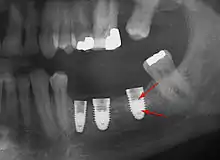

Bone loss (peri-implantitis) on implants over 7 years in a heavy smoker

Fixture show

Fracture of abutment screws (arrow) in 3 implants required removal of the remainder of the screw and replacement.

Cement peri-implantitis

Dental cement under the gingiva causes peri-implantitis and implant failure.